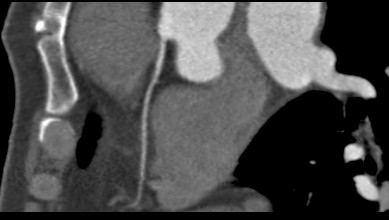

标题: CT24400:患者54岁,心前区不适进行心脏冠脉造影检查。 [打印本页]

标题: CT24400:患者54岁,心前区不适进行心脏冠脉造影检查。

患者54岁,心前区不适进行心脏冠脉造影检查。高手看看有问题没有?